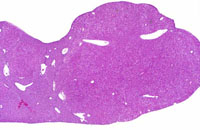

A large and a small nodule of regenerating hepatocytes in an Alb-uPA transgenic mouse.